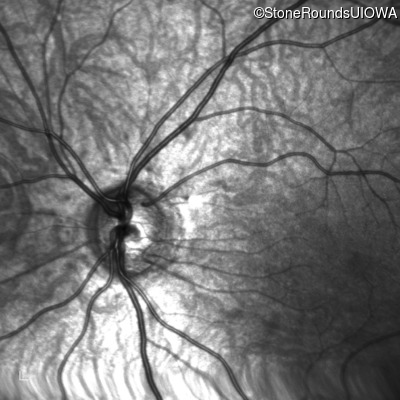

Infrared Fundus Photograph - Right - 10/160 +1 sc

Exemplar

Infrared Fundus Photograph - Left - 10/200 sc